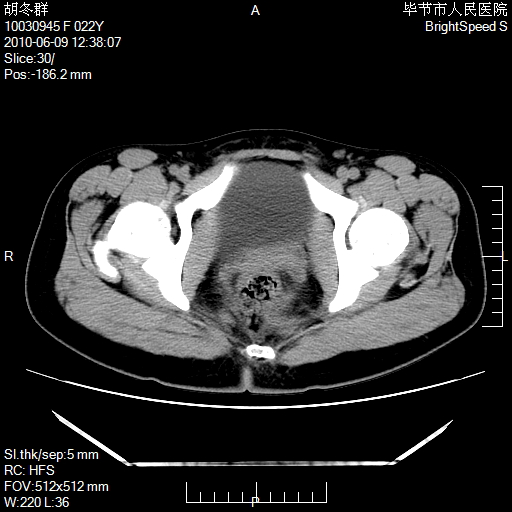

患者23岁,发现腹部包块3月。

左侧卵巢囊腺瘤或囊腺癌

盆腔内囊性占位性病变;考虑左侧卵巢囊腺瘤。

有分隔、壁薄,支持考虑左侧卵巢囊腺瘤。

左侧卵巢浆液性囊腺瘤。

支持考虑左侧卵巢囊腺瘤;宫腔积液。

有分隔、壁薄,支持考虑左侧卵巢囊腺瘤。排尿后,膀胱缩小,由于重力作用,肿块下移就到了膀胱位置,很好理解。